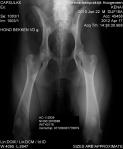

Tänker här visa två exempel på röntgenbilder som i mina ögon är fria, i SKK’s ögon är den ena belastad på en sida…………..

- Denna bild är bedömd A/A och det är förstås helt korrekt. Till trots för att hunden inte ligger rakt.

- Denna bild har bedömts som B/C av SKK. Samma hund har av SKK avlästs med bedömningen A,B,C,D på sina höfter. Vad är rätt?